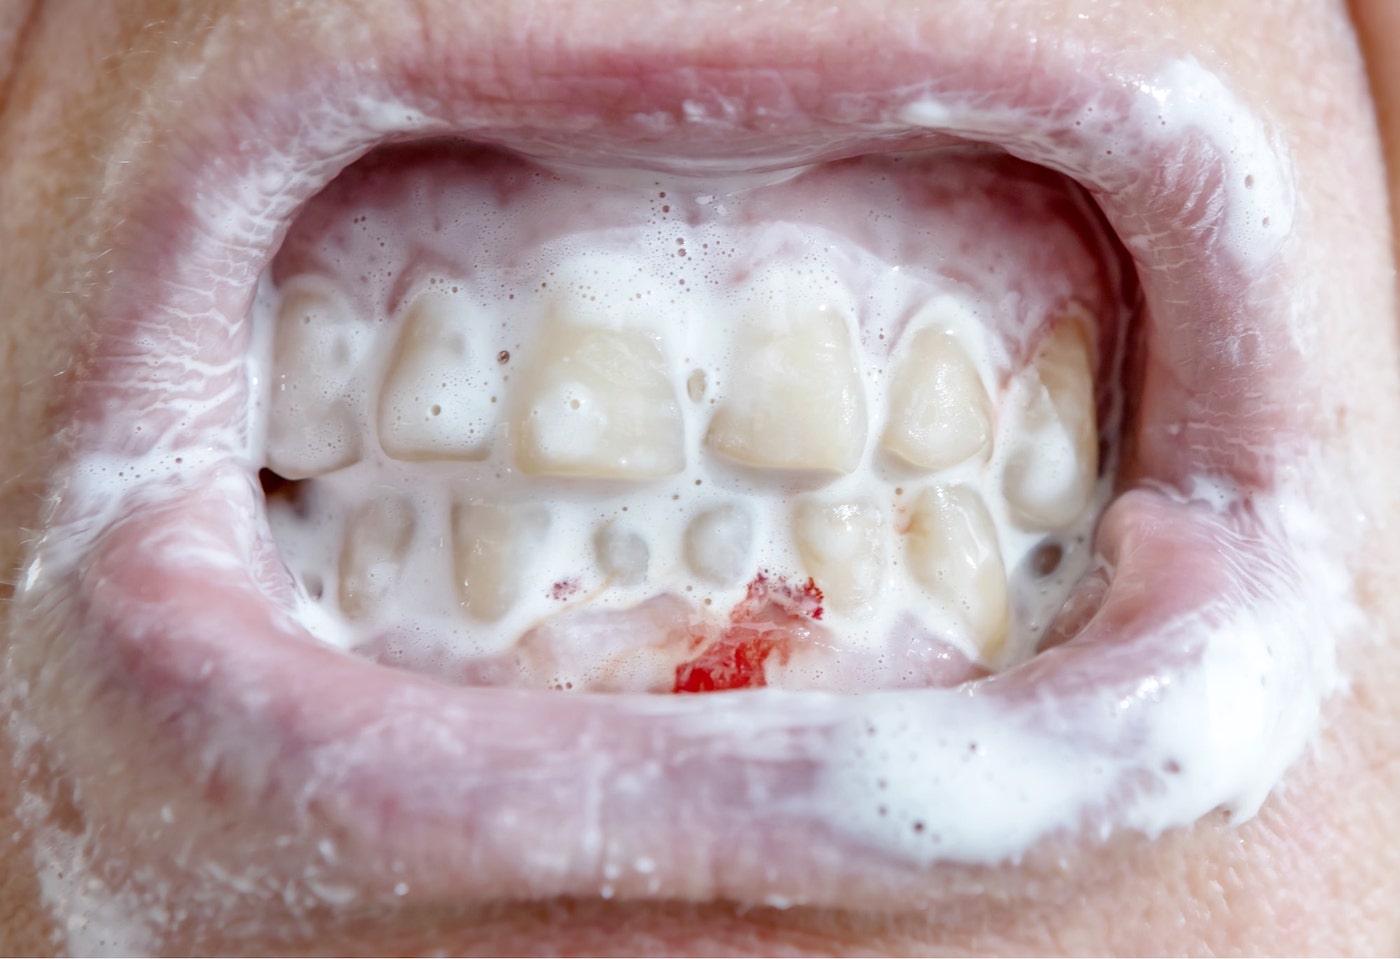

Krwawiące dziąsła - kiedy udać się do periodontologa

Co jest przyczyną krwawienia dziąseł i jak temu zapobiegać? Kiedy niezbędna będzie wizyta u periodontologa?